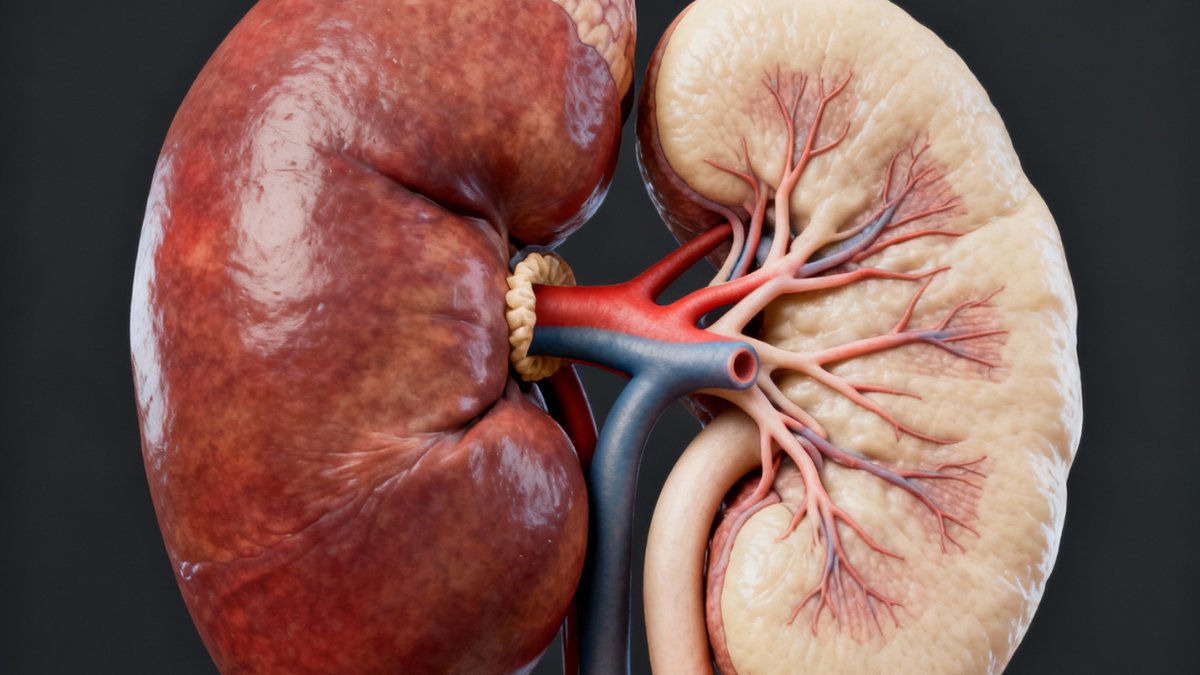

Os rins são órgãos vitais para a eliminação de substâncias nocivas do organismo, e o ser humano conta com dois deles funcionando normalmente para essa tarefa essencial. No entanto, algumas doenças podem comprometer gravemente suas funções.